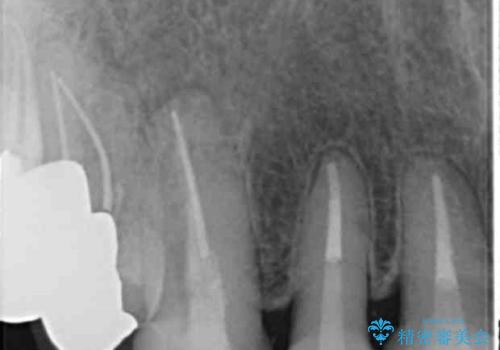

- 前歯のセラミック治療から4年半経過した患者様です。

4年ぶりに来院して下さいました。

治療した上の前歯6本は全く問題なく、「獅子舞みたいだった前歯を綺麗にして下さってありがとうございました!」と再度お礼を言って下さいました。

4年半前のクラウン装着時と変わらず、まるで天然歯のように自然に見えました。

患者様の良好なセルフケアと精密な適合の良いクラウンにより、歯肉の腫脹や退縮も認められませんでした。

4年半前に行った治療に大変ご満足頂き、他の部位の治療のため再来院して下さいました。